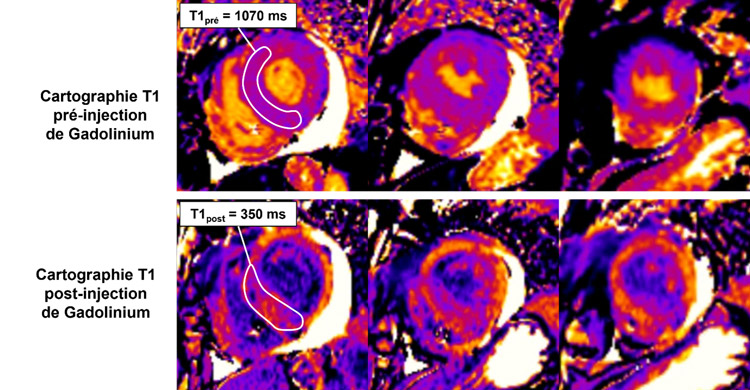

Figure 2 : Cartographie T1 pré et post injection de gadolinium

Coupes petit-axe basal, médian et apical

La mesure de l’hématocrite permet de calculer la formule du volume extracellulaire (ECV) mesuré à 41 %.

Figure 6 : Cartographie T1 pré et post injection de gadolinium - Coupes petit-axe basal, médian et apical

Valeur d’ECV mesurée à 41 %.

- La mesure du T1 mapping à 1 070 ms n’est pas très élevée pour l’âge du patient (norme < 1 100 ms pour cet âge).

- Par contre, la mesure du volume extracellulaire (ECV) est franchement élevée à 41 % (norme < 27 %).

- À noter que cette divergence entre T1 mapping normal et ECV élevé peut notamment être décrite chez les patients avec amylose cardiaque.